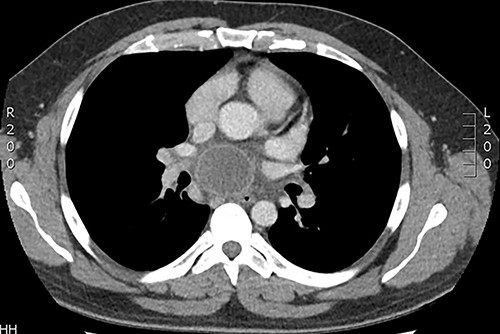

The second case was a 31-year-old gentleman otherwise fit and well was admitted to hospital with community acquired pneumonia and underwent intravenous antibiotic therapy. CT imaging demonstrated mediastinal lymphadenopathy and an incidental large subcarinal mass. The patient underwent EBUS biopsy of the subcarinal mass, which did not retrieve any tissue. Following discharge from hospital the patient represented 5 days later with pyrexia and chest pain. Repeat CT imaging demonstrated a rim enhancing lesion with cystic features and indenting the right pulmonary artery (Fig. 2). The patient was commenced on broad spectrum antibiotic therapy however remained pyrexial with rising inflammatory markers and was transferred to our institution for urgent surgery. The patient underwent urgent right posterolateral thoracotomy and deroofing of mediastinal cyst. Operative findings were that of an infected subcarinal cyst with pus within the cyst and dense adhesions to the surrounding structures. The cyst was excised from the surrounding structures and de-roofed. The patient returned to the high dependency unit in a stable condition and progressed satisfactorily eventually discharged from hospital 7 days following admission. Post-operative histology was consistent with an infected bronchogenic cyst and pus cells with no growth on culture.